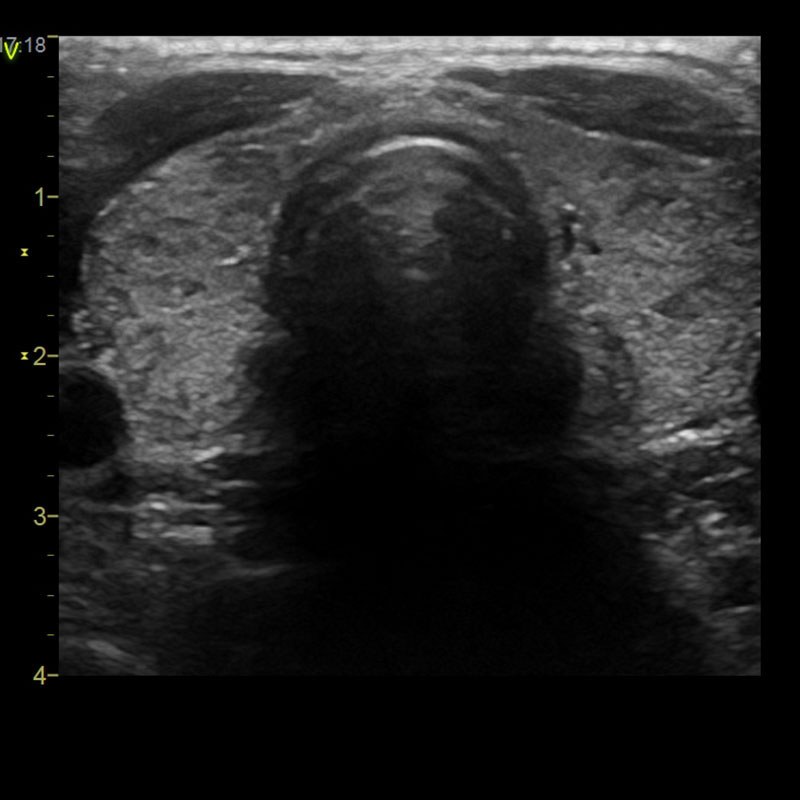

Die Ultraschalluntersuchung der Schilddrüse dient der Beurteilung von Struktur und Größe des Organs.

Bei der Struktur interessiert uns vor allem, ob Schilddrüsenknoten vorhanden sind. Unter diesen unterscheiden wir solide (gewebliche) und zystische Knoten. Schilddrüsenzysten bleiben in der Regel ohne Konsequenz. Selten kann es zu spontanen Einblutungen in die Zysten kommen, was zwar zu einer plötzlichen und oft beeindruckenden Schwellung führen kann, aber ungefährlich ist. Bei geweblichen Knoten hängt die weitere Verfahrensweise wiederum von der Knotenstruktur ab. Verkalkte, sogenannte degenerative Knoten, bleiben ohne unmittelbare Konsequenz. Bei anderen geweblichen Knoten kann eine Punktion zur Krebsvorsorge oder eine nuklearmedizinische Untersuchung (Schilddrüsenszintigraphie) zur Beurteilung der Knotenfunktion erforderlich werden. In dieser Untersuchung kann man sogenannte autonome Knoten identifizieren, die zu unkontrollierter Hormonproduktion neigen und dadurch zur Schilddrüsenüberfunktion führen können. Diese Schilddrüsenautonomien können dann in den meisten Fällen durch eine Radiojodtherapie behandelt werden.